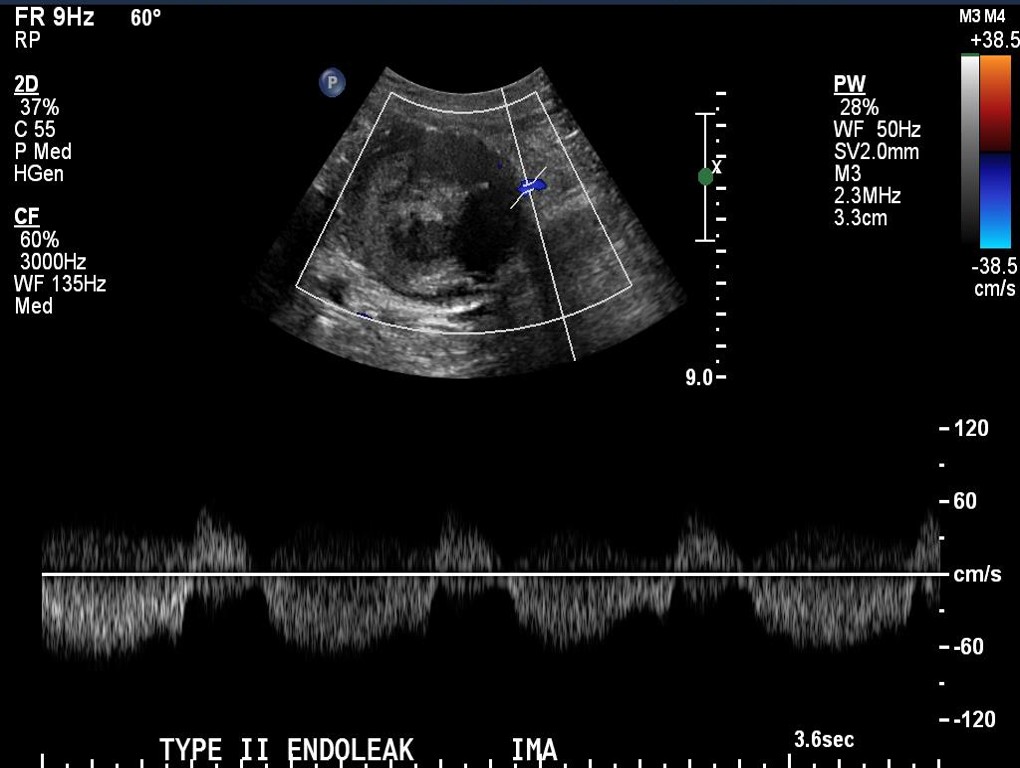

The embolization with NBCA sealed the IMA and the cavity in the AAA sac. This was checked with intraoperative duplex, done with a transabdominal aortic probe.

Transabdominal aortic duplex is easier on sleeping patient and potentially gives more information than arteriography alone. The patient in followup had no endoleak and demonstrated sac shrinkage.